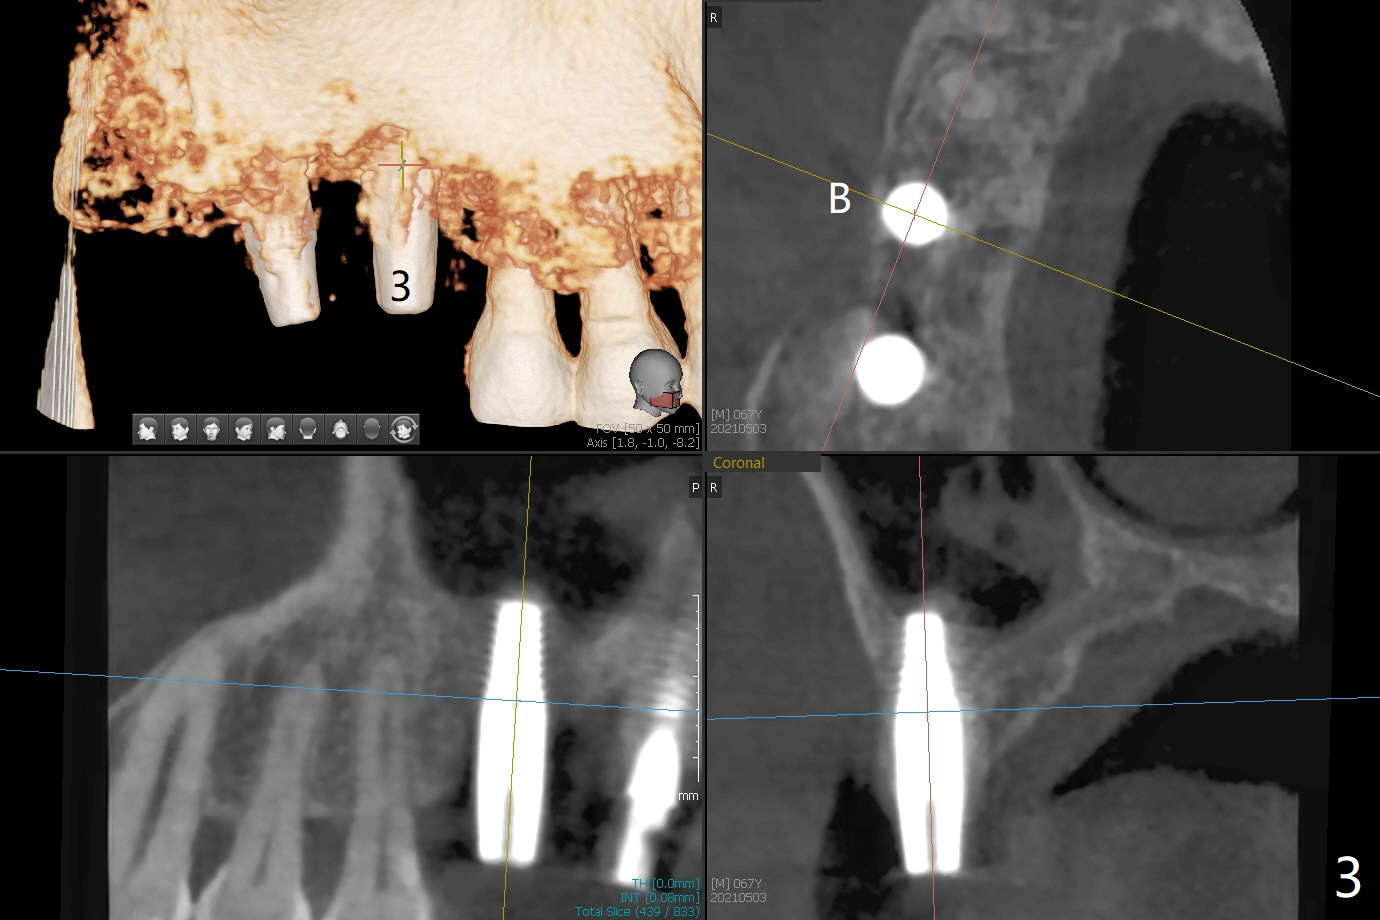

尽管2号牙植体比设计长,上颌窦提升顺利(图一,二)。虽然3号牙植体颊侧仍有骨质(图三:B),由于近中骨质多,徒手植入时植体远中偏移(图一:红箭头)。术后一个月树脂敷料撤除,2号牙牙槽窝,3号牙伤口愈合(图四)。